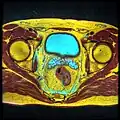

Imágenes adicionales hipófisis

Vesículas seminales vistas en una resonancia magnética a través de la pelvis. La zona grande de color cian es la vejiga, y las estructuras lobuladas más pequeñas situadas debajo son las vesículas.

Vesículas seminales vistas en una resonancia magnética a través de la pelvis. La zona grande de color cian es la vejiga, y las estructuras lobuladas más pequeñas situadas debajo son las vesículas. -